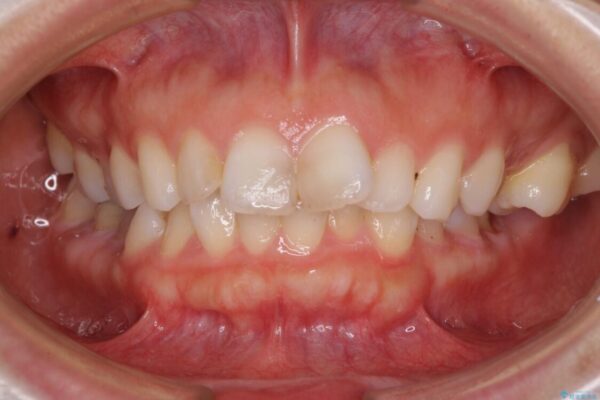

口元の閉じにくさと、奥歯の咬み合わせを気にして来院された患者様です。

左下の大臼歯2本が顕著に舌側に傾斜しているため、まずは奥歯の咬み合わせを改善をし、その後上下左右の第1小臼歯4本を抜歯することで口元を引っ込めながら整えることとしました。

治療前

• 【モニター】出っ歯と咬み合わせを改善 ワイヤー装置の抜歯矯正 治療前画像